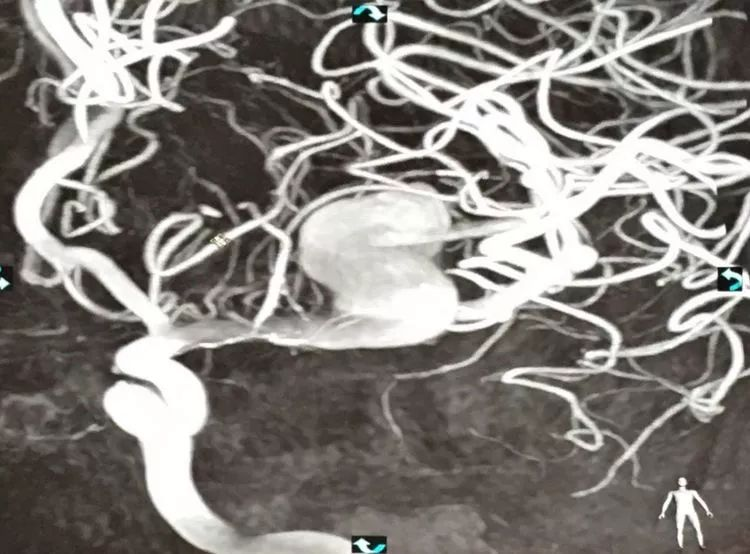

CASE 1 DAVF

-动脉入路栓塞:颈内动脉脑膜垂体干;大脑后动脉的硬膜供血分支

-可解脱的Apollo微导管(3cm,1.5cm)

-栓塞材料是PHIL,CT伪影小

-DAVF含有软膜血管的供血,有医生提出可能需先栓塞,但多数专家包括Wakhloo,Civan等认为这些供血最终还是供应到硬膜上的,也就是说软膜血管没有直接瘘到静脉,它们之间还有硬模膜上的动脉,软膜血管只是近端的供血动脉,他们认为不栓塞软膜供血动脉而通过硬模膜供血完全闭塞静脉端应该可行